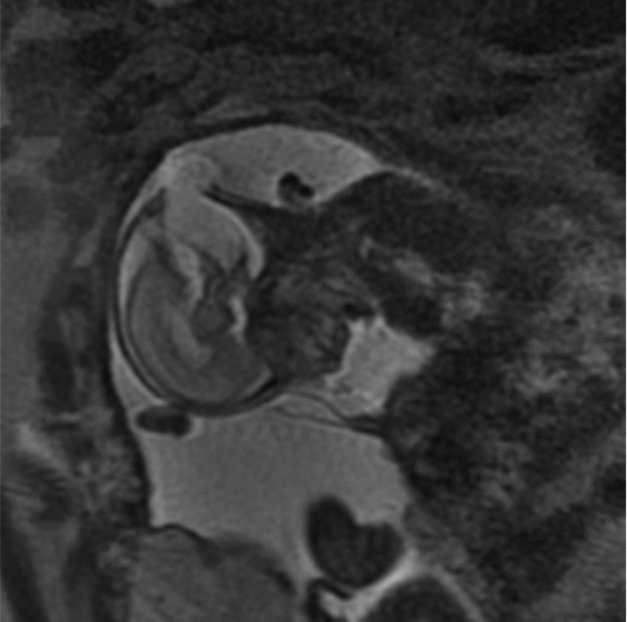

Between 2004 and 2014, there were over 1,800 twin pregnancies managed at our hospital. Thirteen were complicated by a discordant NTD: eight with anencephaly, three with an encephalocoele, and two with spina bifida. Nine of the 13 pregnancies were DCDA, three were MCDA, and one was MCMA. The mean gestation at diagnosis was 13.7 weeks (SD 1.0) for anencephaly, 18.1 weeks (SD 0.4) for spina bifida, and 20.4 weeks (SD 3.2) for encephalocoele. Figure 1 shows an ultrasound image of a twin pregnancy discordant for encephalocoele. Among cases with a NTD, six affected fetuses and three unaffected co-twins had diagnostic genetic testing and all were found to have a normal karyotype.

FIGURE 1 MRI of twin with encephalocoele.